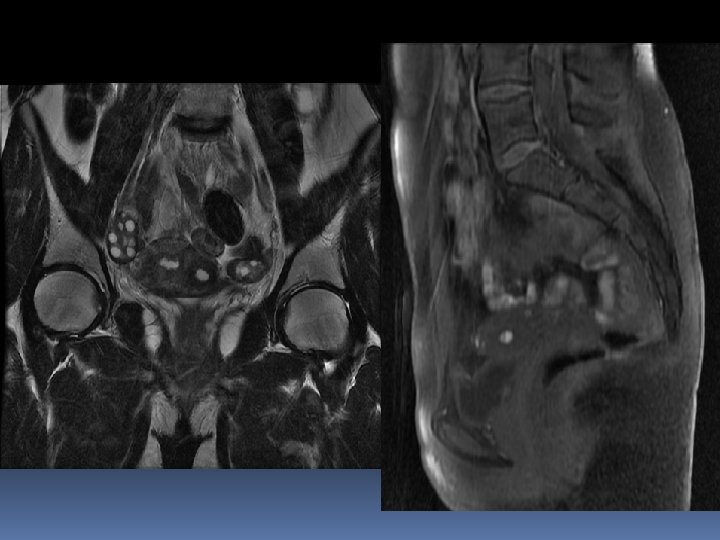

Netta prevalenza di forme pluricompartimentali

Altre localizzazioni L’endometriosi profonda può coinvolgere, anche isolatamente parete addominale anteriore vagina fossa ischio-anale spazi presacrale e pre-coccigeo perineo nervi pelvici Quasi sempre le localizzazioni insolite si accompagnano a lesioni in sedi tipiche

Endometriosi dei nervi pelvici L’entrapment può interessare i nervi sciatico, otturatorio, femorale, pudendo, ipogastrico inferiore e plesso lombosacrale; decorso interamente extra-peritoneale → patogenesi? L’ipotesi della mestruazione retrograda perde forza rispetto ad altre disseminazione linfatica o vascolare teoria neurale (rilascio di neurotrasmettitori con induzione dell’angiogenesi) infiltrazione diretta di parametrio, spazio presacrale, parete pelvica e plessi da lesioni retrocervicali